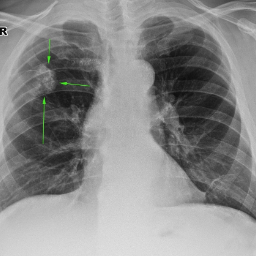

Фиброз Легких На Рентгене Фото

Фиброз Легких На Рентгене Фото 115 фотографий